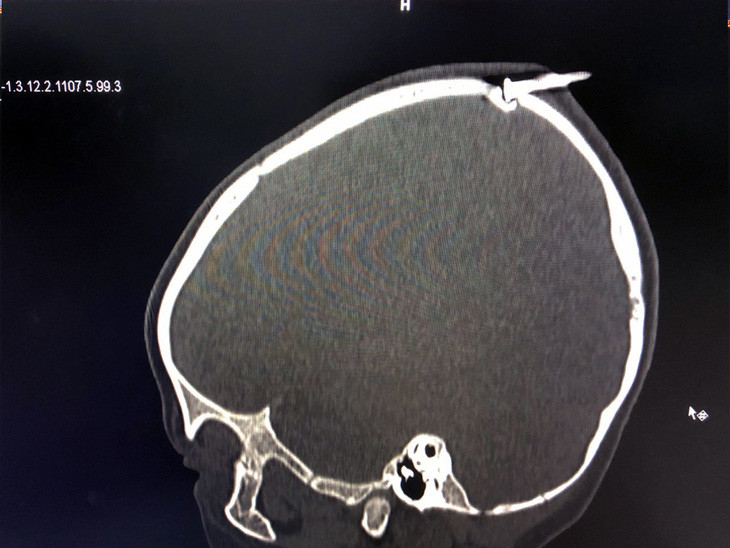

| Cây đinh sắt đâm vào đỉnh đầu bé trai 2 tuổi làm lún xương sọ. Ảnh: Bệnh viện cung cấp |

Sau khi sơ cứu, người nhà lập tức đưa cháu xuống Bệnh viện Nhi Đồng Nai cấp cứu với tình trạng xuất huyết vùng đầu. Qua chụp CT Scanner, bác sĩ phát hiện cây đinh sắt dài khoảng 3 cm đâm vào đầu của bé trai. Đầu mũi đinh đâm lún xương sọ, gây nguy cơ rách màng cứng, tổn thương não. Bệnh nhi lập tức được phẫu thuật cấp cứu khẩn cấp và rút cây đinh khỏi đầu.